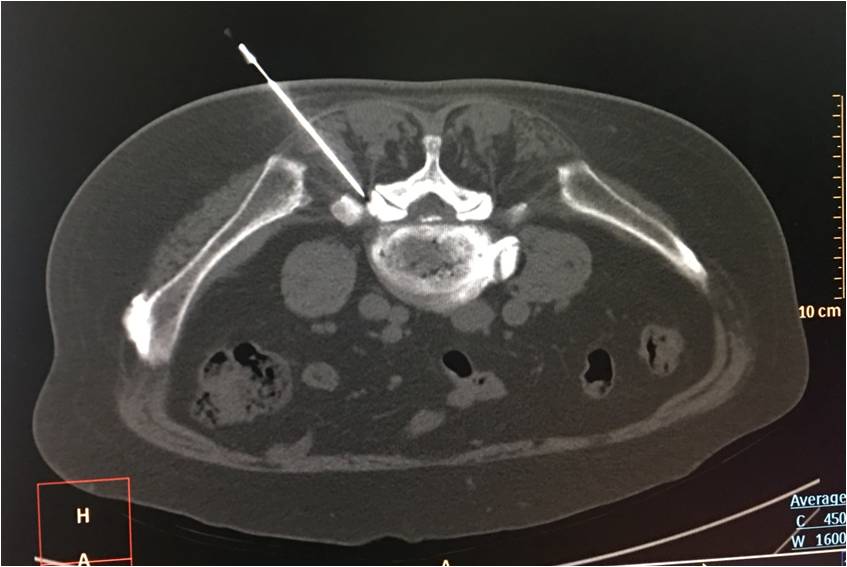

超声下引导体横下韧带针刀松解方法:固定好超声探头,穿刺点处给予0.5%利多卡因进行局部麻醉。用汉章牌3号1.0规格针刀(1.0mm×80mm),刀口与身体长轴平行,采用平面内穿刺,外侧入路,在超声实时引导下刺入皮下,缓慢深入,观察针尖准确触及横突上缘呈中强回声的窄薄层区,此时可感到针下为纤维样坚韧组织。

继续缓慢进针穿过该组织后,可感到针下触及坚硬骨质。在此区域由外上向内下纵向铲切,针下触及骨质后略退针并重复上述铲切操作(约4-5次),幅度不超过3mm,铲切全程必须保证可明确观察到针尖位置。操作过程中如果患者有触电感、剧烈疼痛等不适时,立即停止进针、松解等操作。

针下有松动感后即可出针,出针后可见目标区域回声强度减弱。针孔部按压3分钟,以无菌敷料贴敷穿刺点,治疗结束。嘱患者平卧休息30分钟。